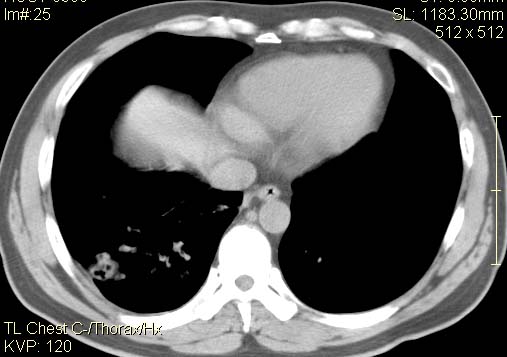

以下是引用qc80012345在2007-4-17 12:33:00的发言:[br]右肺下叶周围型肺癌伴肺门及纵隔内淋巴结转移;比较清楚。

以下是引用qingyuan在2007-4-17 14:19:00的发言:[br]右肺下叶外侧后段胸膜下区节结样病变、分叶、内可见空洞,壁厚薄不均,胸膜凹陷、肺门周围区纹理增粗、僵硬、并近似小结节样改变,肺门区软组织节结、纵膈淋巴结肿大,患者病史长、抗炎治疗无好转炎性改变基本排除,考虑:右肺下叶周围型肺癌伴纵膈及右肺门区淋巴结转移、肺内淋巴管受侵。